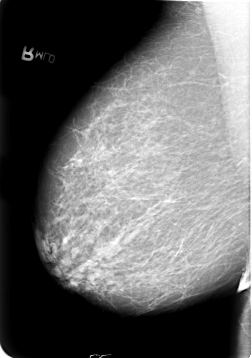

B_3021_1.LEFT_MLO

FILE: B_3021_1.LEFT_CC.OVERLAY

TOTAL_ABNORMALITIES 3

ABNORMALITY 1

LESION_TYPE MASS SHAPE LOBULATED MARGINS CIRCUMSCRIBED-ILL_DEFINED

ASSESSMENT 3

SUBTLETY 3

PATHOLOGY MALIGNANT

TOTAL_OUTLINES 1

BOUNDARY

ABNORMALITY 2

ABNORMALITY 3